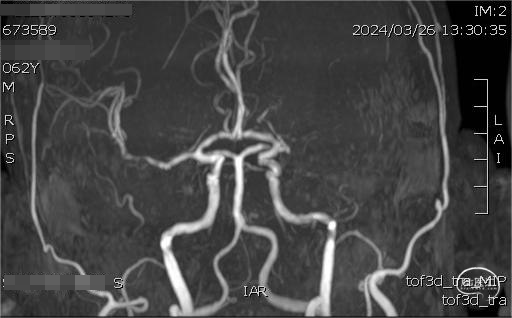

左侧大脑中动脉闭塞,左侧大脑中动脉供血区存在低灌注区。

➢ 头颅高分辨磁共振

管壁高分辨磁共振提示闭塞段斑块有强化,闭塞段不长。